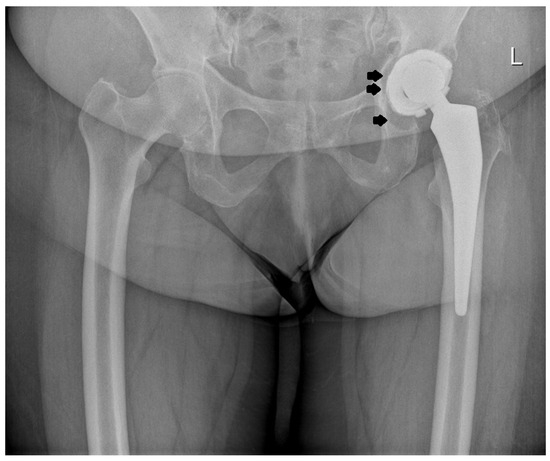

2.2. Design of the L-Cup Acetabular Component

3. Results

4. Discussion